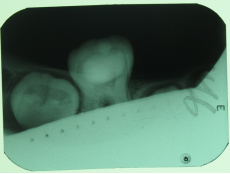

根管治疗前中后

2.不拍牙片能治疗牙齿吗?

能!一些基础性的常见病…是可以的。(很少遇见)

但是稍微复杂性的牙病,必须拍片!拍牙片是为了让患者得到一种保障,提高医生诊断的准确性和成功率。如果不拍片的话,有可能导致治疗过程中无法正确把握位置等情况出现,从而影响治疗效果。